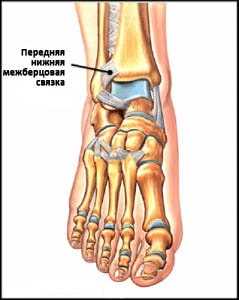

Пример повреждения связок голеностопа. Травма передней межберцовой связки

Существует три группы связок, принимающих участие в фиксации голеностопного сустава. По наружной поверхности сустава расположены пяточно-малоберцовая, передняя и задняя таранно-малоберцовая связки, которые проходят вдоль наружной лодыжки и удерживают таранную кость от бокового смещения.

По внутренней поверхности сустава проходит дельтовидная (внутренняя коллатеральная) связка, состоящая из глубокого и поверхностного слоев. Поверхностный слой крепится к таранной и ладьевидной костям, глубокий - к внутренней части таранной кости. Третья группа связок, представленная межберцовым синдесмозом, задней поперечной, задними и передними межберцовыми связками, соединяет берцовые кости между собой. Чаще всего встречается повреждение наружной группы связок, обычно страдает передняя таранно-малоберцовая связка.

Передняя нижняя межберцовая связка (далее ПНМС), отвечающая за стабилизацию U-образной «вилки» берцовых костей, подвергается травмированию в случае ротации зафиксированной на той или иной поверхности стопы. Зачастую, образующийся после заживления данного вида связки рубец, может спровоцировать развитие импинджмента.

Рис. 5 Анатомия ПНМС